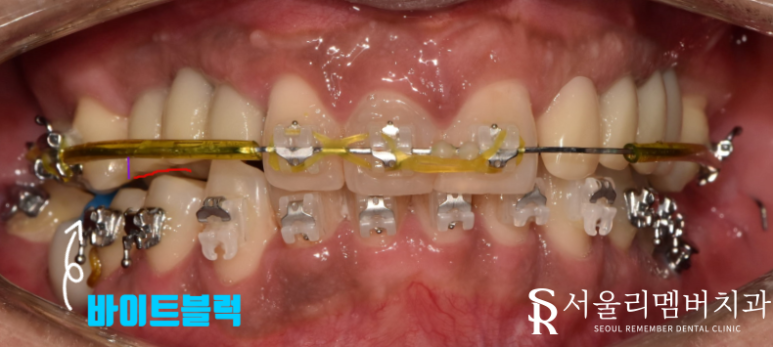

자, 이제 삐뚤빼뚤 대칭이 맞지 않는 좌, 우측을 어느 정도 기준을 세워 맞춰줘야 되는데요.

잇몸에 식립해 이동력을 얻는 미니스크류의 도움을 받아 제위치로 교정을 진행했습니다.

배열이 정돈되었다면 임플란트를 심을 준비를 해야겠죠?

교정이 진행되고 있는 동시에 픽스쳐를 식립했습니다.

아무래도 두 가지가 함께 이루어지기 때문에 환자께서 느끼는 피로감이 걱정이 되었는데요.

다행히 환자께서 협조를 잘해주신 덕에 수월하게 진행할 수 있었습니다.

총 8개의 픽스쳐 식립을 마무리 지었네요ㅎㅎ

남성역 치과 에서는 심어진 임플란트 주위로 교합이나 옆 인접치와의 위치 관계 등 세밀한 부분을 조정해 주었습니다.

여기서 한 가지 알아둬야 될 것은 임플란트는 이동이 불가합니다.

그래서 미리 교정을 통해 치열을 정돈해야 되는 거죠.

교합은 조정을 통해 맞출 수 있는 부분이나.. 배열의 문제는 미리 해결을 한 뒤에 식립을 해야 됩니다.

어금니에 바이트 블럭이라는 파란색 레진의 도움을 받아 교합 간섭을 막아주었습니다.

보다 정밀한 교합관계를 개선하기 위해 필요하죠.